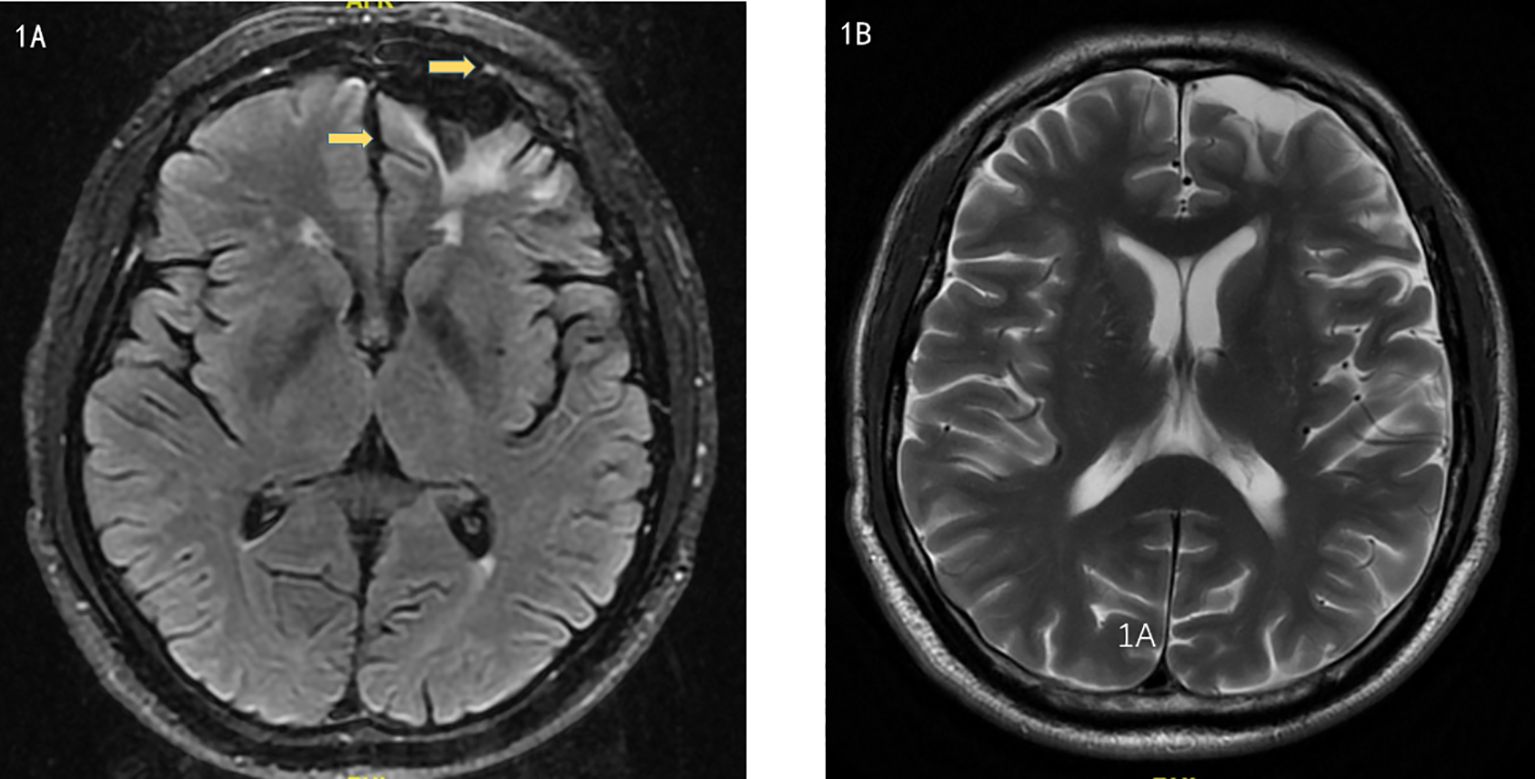

Brain MRI indicated multiple small ischemic lesions and a softening lesion in the left frontal lobe (Figures 1A, B). Imaging studies included ultrasound, revealing right lateral epicondylitis and right knee effusion (Figure 2). Echocardiography identified severe pulmonary hypertension and widened pulmonary arteries with findings consistent with congenital heart disease following ventricular septal defect repair.

Figure 1. (A, B). Magnetic Resonance Imaging showed multiple small ischemic lesions in the brain and a softening lesion in the left frontal lobe.